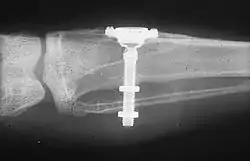

Dental implants are used in orthodontic patients to replace missing teeth (as above) or as a temporary anchorage device (TAD) to facilitate orthodontic movement by providing an additional anchorage point.[16][18] For teeth to move, a force must be applied to them in the direction of the desired movement. The force stimulates cells in the periodontal ligament to cause bone remodeling, removing bone in the direction of travel of the tooth and adding it to the space created. In order to generate a force on a tooth, an anchor point (something that will not move) is needed. Since implants do not have a periodontal ligament, and bone remodelling will not be stimulated when tension is applied, they are ideal anchor points in orthodontics. Typically, implants designed for orthodontic movement are small and do not fully osseointegrate, allowing easy removal following treatment.[19] They are indicated when needing to shorten treatment time, or as an alternative to extra-oral anchorage. Mini-implants are frequently placed between the roots of teeth, but may also be sited in the roof of the mouth. They are then connected to a fixed brace to help move the teeth.